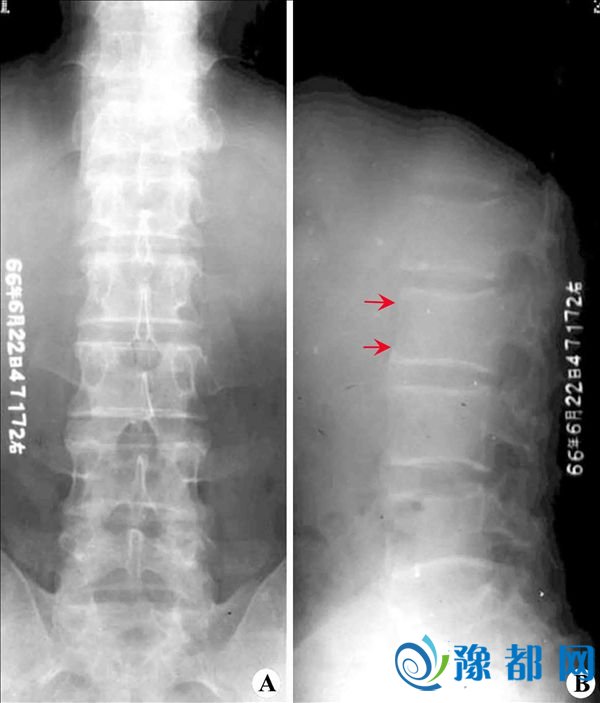

生活中越来越多的人患上了强直性脊柱炎,这个病会让患者的身体变形,从而影响着他们的正常生活,因此我们要多注意预防,尤其是青少年时期,脊柱变形不仅影响孩子的健康成长,更是会使孩子受到别人的嘲讽,影响心理健康,因此我们要注意远离强直性脊柱炎,那么在日常生活中我们应该如何预防强直性脊柱炎这种疾病呢?

强直性脊柱炎 强直性脊柱炎预防 强直性脊柱炎的病因